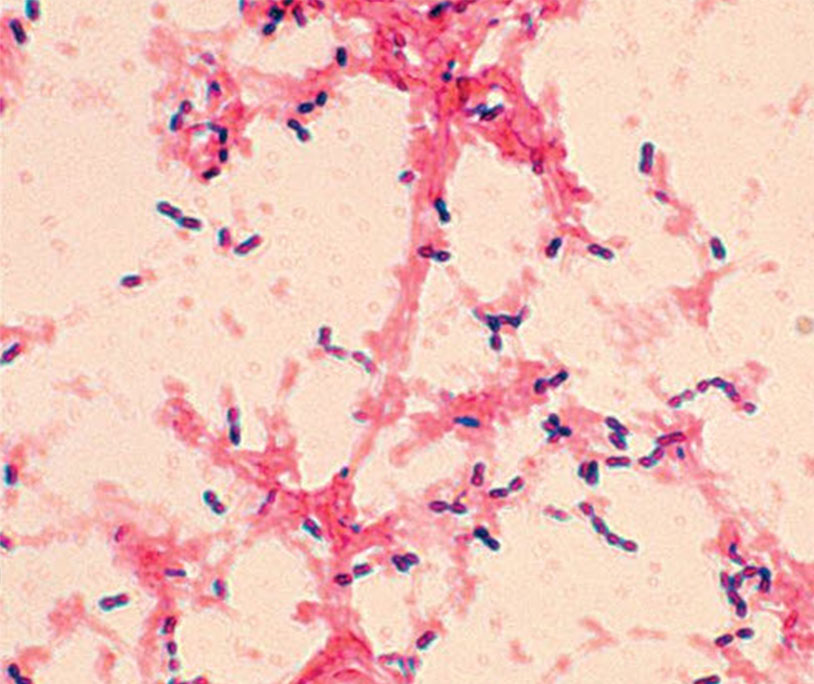

Your Gram stain is complete and correct. Which of the following statements would apply to the image you see?

Your Gram stain is complete and correct. Which of the following would apply to the image you see?